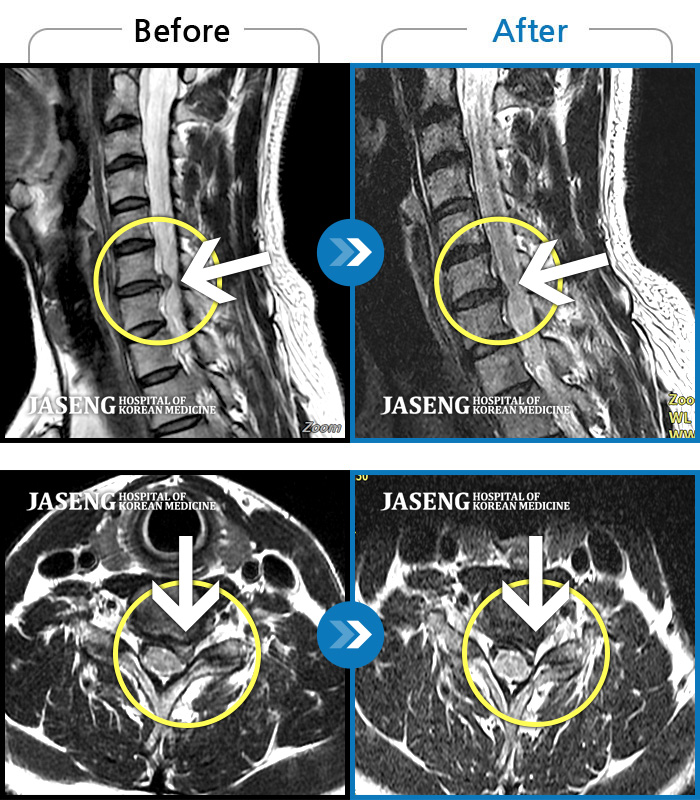

MRI 치료사례

좌측 목, 어깨, 상지 찌릿한 방사통으로 일상생활 지장, 야간통이 심하다